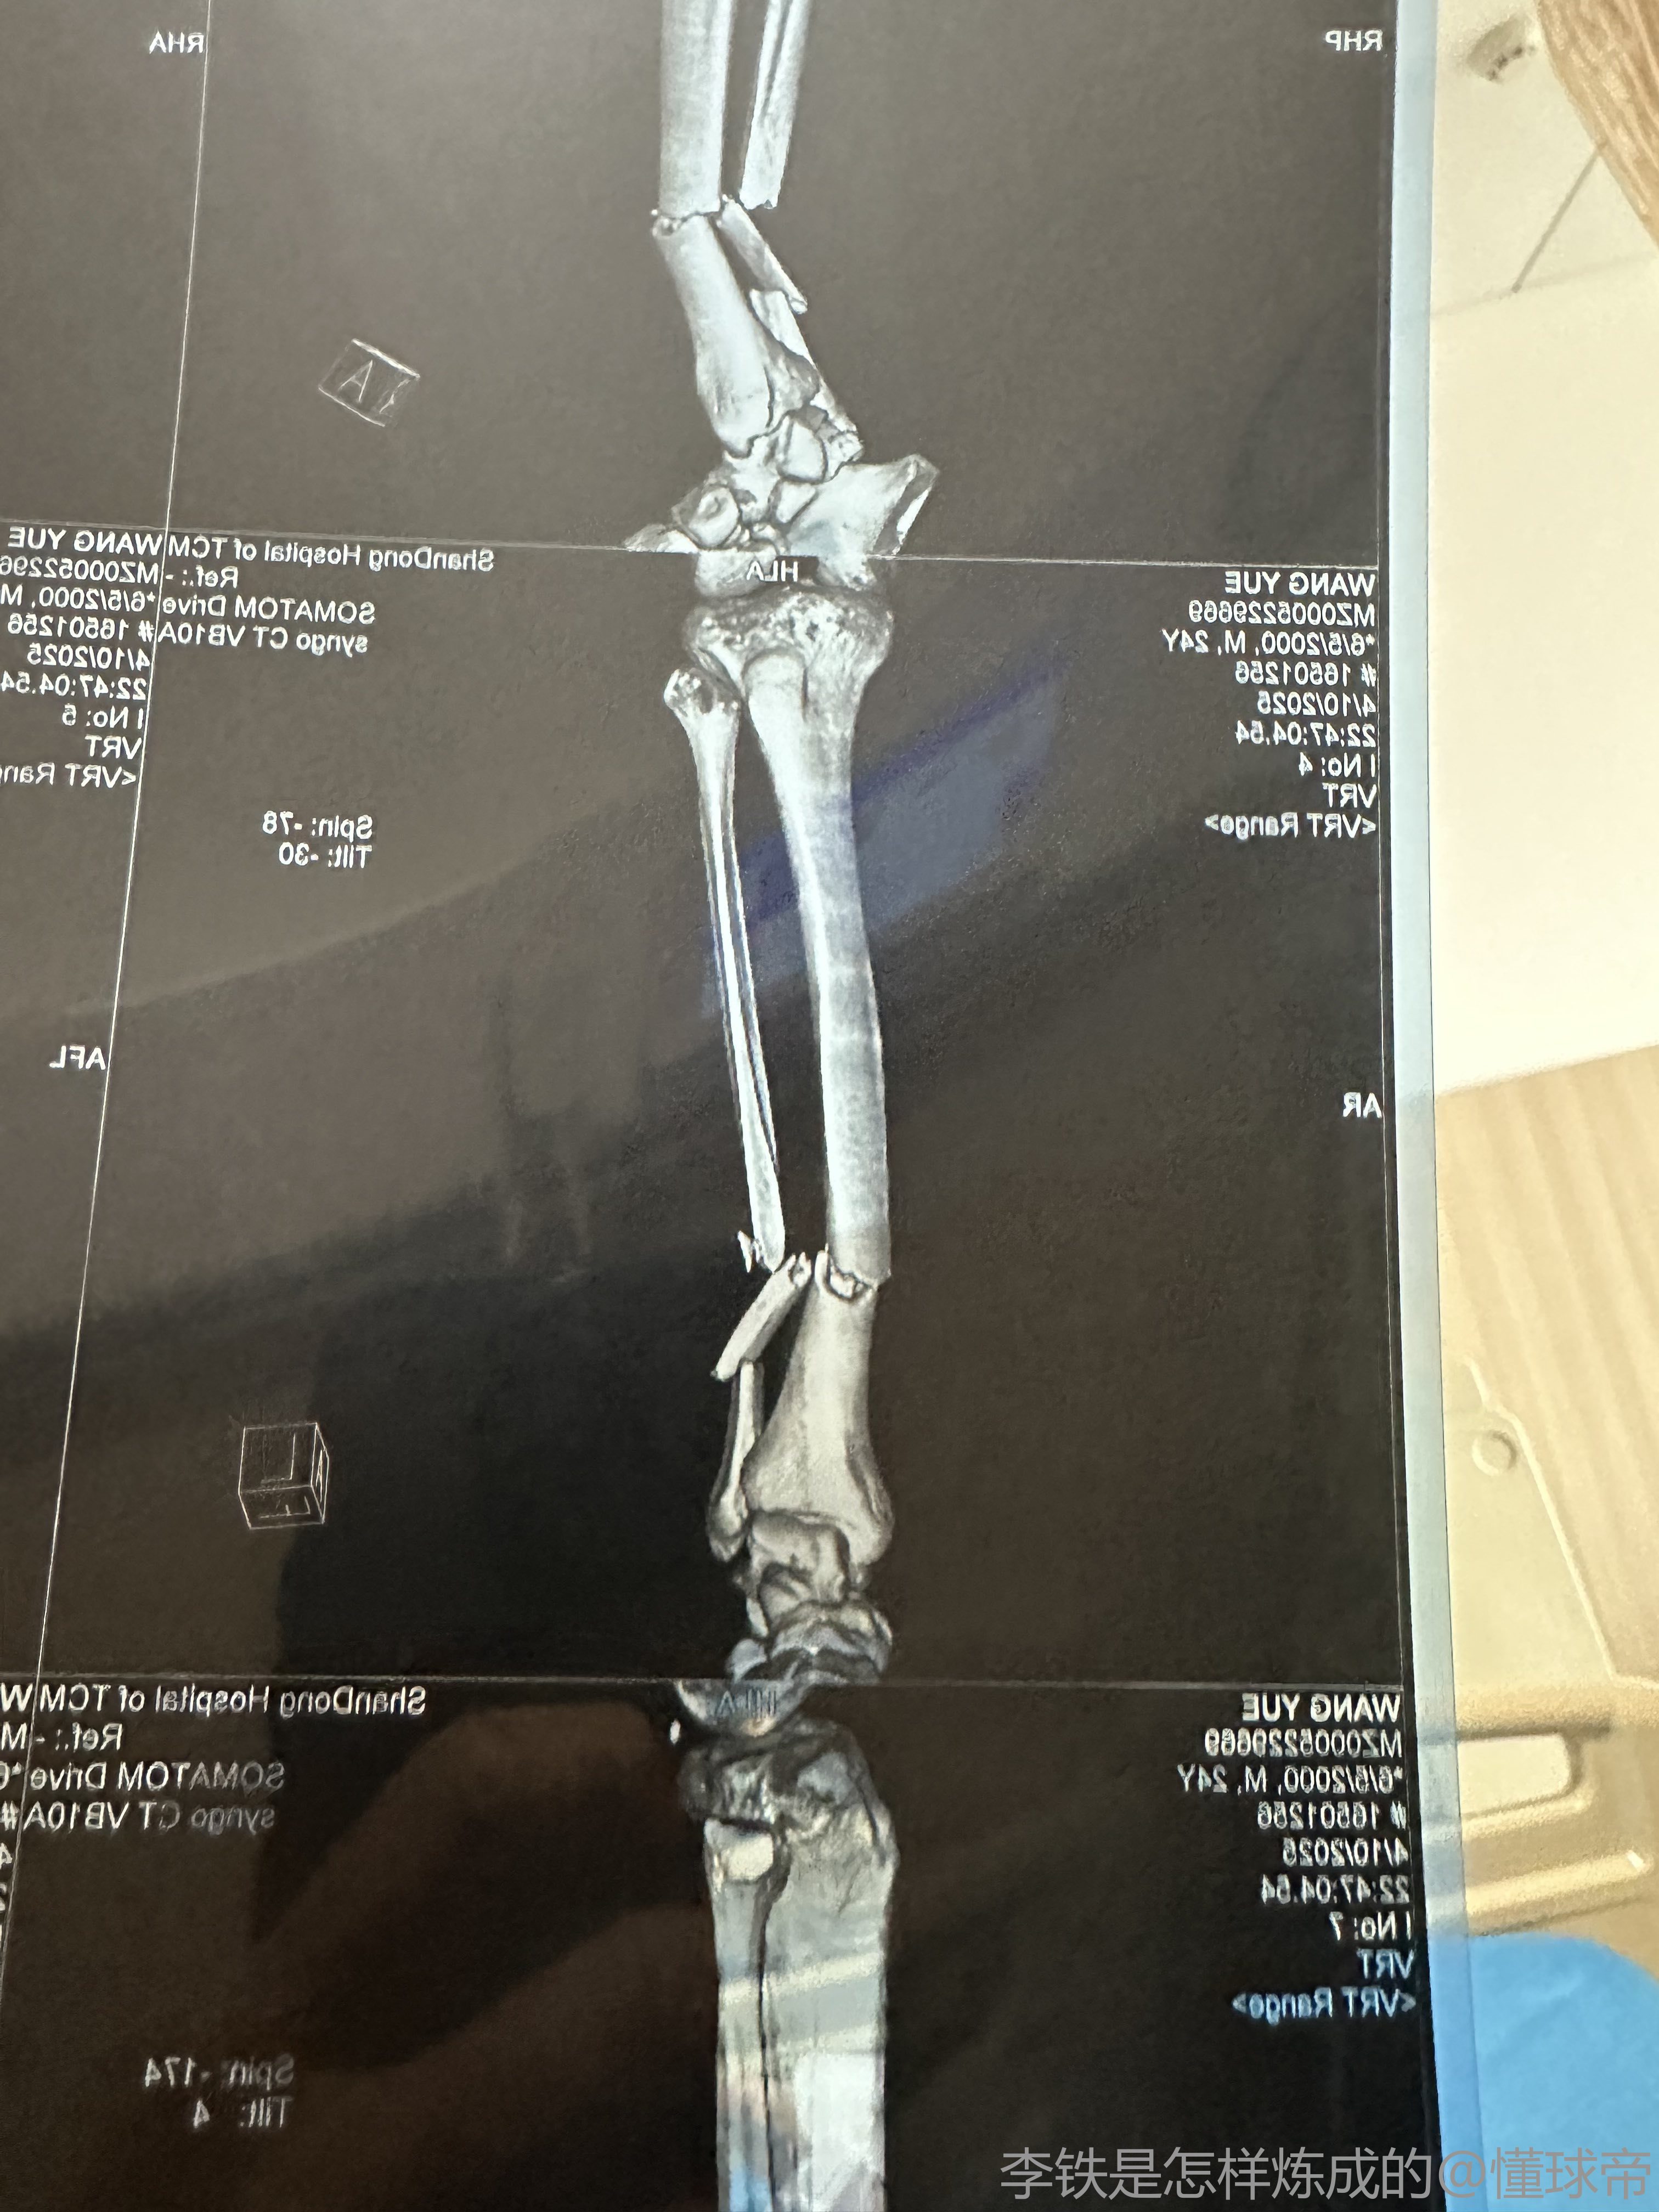

据记者牛志明的消息,山东泰山B队中场艾孜海尔初步诊断为右胫腓骨中段骨折。

牛志明写道:在昨晚山东泰山B队对阵兰州比赛中受伤的艾孜海尔,初步诊断是右胫腓骨中段骨折,今天等专家会诊后确定治疗方案。泰山队会给他提供最好的治疗和康复支持,祝福小伙子早日康复。

去年4月份踢球也是胫腓骨中段骨折,当时的场景至今忘不了,所以球员的心理创伤永远大于身体上的创伤,但好在现在医疗手段十分发达,这种的骨折在医院里都有微创做饭,我是4个月就可以下地走路,我的主治医师是给张驰做手术的医生,如果手术完成后接受专业的康复训练,4个月就能接受低强度的训练,但是会有一根长的钢钉留在腿里,不耽误正常的运动,张驰在青岛踢的那一年腿里就一直有,等着以后可以在拆出来,其实在某种意义上骨头断了也是一种好事,因为骨头是可以百分百痊愈的,但韧带肌肉不可以,还是那句话,康复后球员需要很长的时间走出心理阴影,能做到和张驰一样就非常厉害了,最后祝小艾早日康复,走出心魔